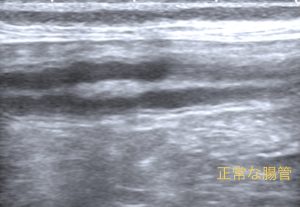

こんにちは。獣医師の永井です。 今回は肉芽腫性腸炎についてです。 肉芽腫性腸炎は、稀な疾患であり、回腸と大腸に…]]>

こんにちは。獣医師の永井です。 今回は肉芽腫性腸炎についてです。 肉芽腫性腸炎は、稀な疾患であり、回腸と大腸に…]]>